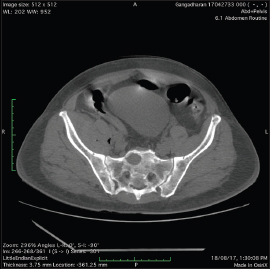

Serum-free kappa light chain was normal, but serum-free lambda was 25.1 mg/dl (elevated) with altered free kappa lambda ratio. Beta-2 macroglobulin was 5.57 which was elevated indicating stage 3 of the disease. In view of right-sided basal crepitations, computed tomography (CT) of the thorax was done, which showed bilateral lower lobe lung parenchymal opacities with pleural effusion and multiple lytic lesions in the spine. As the spleen was just palpable with diffuse tenderness, CT of the abdomen was done which showed thickening with air density pockets in the right psoas and iliacus muscle and splenomegaly and multiple lytic lesions in the vertebral column with pathological fractures [Figure 2], [Figure 3], [Figure 4], [Figure 5]. As this patient also had significant skin manifestations, suspicion toward osteosclerotic myeloma/Crow-Fukase syndrome was made. Hence, the patient was worked up [Figure 6].

| Figure. 4 Computed tomography of the abdomen showing splenomegaly

| Figure. 5 Computed tomography of the abdomen showed thickening with air density pockets in the right psoas and iliacus muscle and splenomegaly and multiple lytic lesions in the vertebral column with pathological fractures